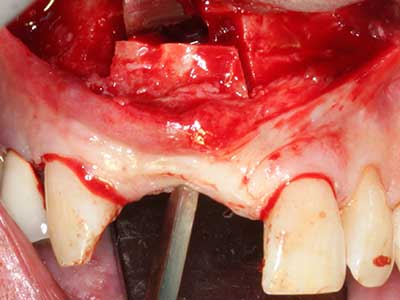

Костната тъкан е не само минерализирана структура, тя съдържа и съществено количество колагенови влакна. Това означава, че тя има не само добра компресивна сила, но и известна степен на гъвкавост, която може да се възприеме като предимство при извършване на костна аугментация. В класическата процедура по разширяване чрез костно разделяне, атрофиралият алвеоларен гребен е разделен надлъжно и внимателно разширен след достигане на подходящата остеотомна дълбочина (Фиг. 13-16), в идеалния случай без допълнително отстраняване на периостеума (Brugnami, Caiazzo et al. 2014, Stricker, Fleiner et al. 2014). Системите с винт и пластини с увеличаване на разстоянието при разширяване са доказали ефективността си при разделяне на двете костни ламели, оставайки под прага на фрактурите. В общи линии, оставащата ширина на костта от поне 3–4 mm е задължителна (Chiapasco, Zaniboni et al. 2006), за да се гарантира добра гъвкавост и достатъчно костно покритие за бъдещото поставяне на импланти. Ако е необходимо, вертикалната остеотомия на едната или двете страни може да подобри гъвкавостта. Комбинацията с допълнителни техники за аугментация, особено в букалната страна, е описана като алтернатива на класическата техника.

Процедурата по разделяне е атравматична и няма голяма загуба на пространство, използвайки пиезотриони, и няма значителна разлика между импланти в разделени челюсти и импланти в алвеоларния гребен без костен дефицит (Chiapasco, Zaniboni et al. 2006, Danza, Guidi et al. 2009). Въпреки това, важно е да има достатъчно и продължително охлаждане, особено при ограничено и дълбоко разделяне, за да се избегне термичен стрес в апикално-остеотомните зони.